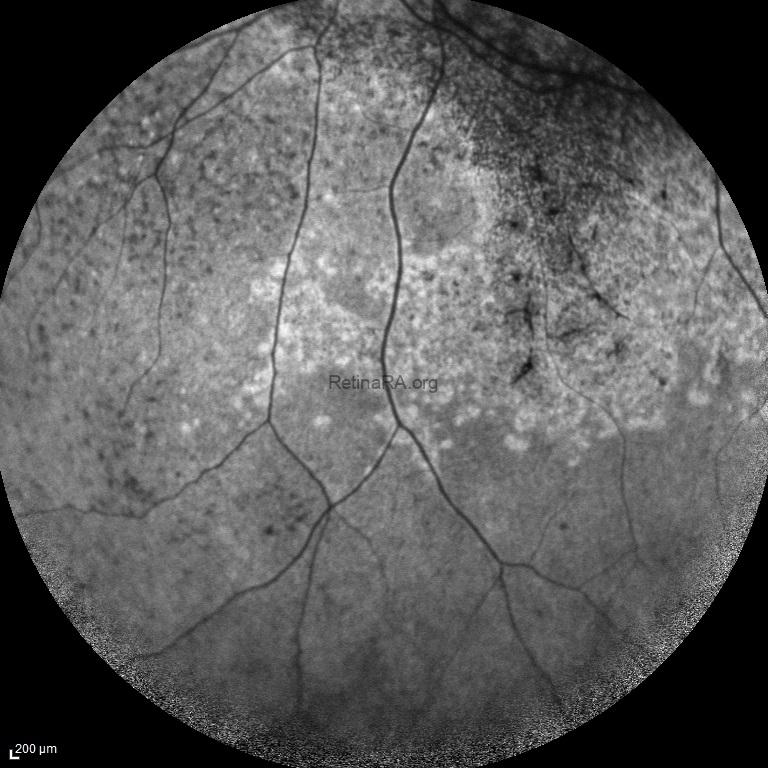

Autofluorescence imaging showed peripapillary sparing in addition to central hypoautofluorescence lesions and ring-like hyperautofluorescence at the outer edge of these lesions. There were also some hypoautofluorescence lesions in the mid periphery but no fleck retinopathy appeared.

Autofluorescence images of severe ABCA-4 retinopathy